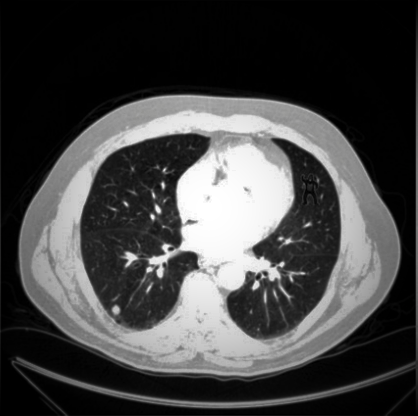

To make this article more fun, let us first try to perform an interesting task. Below is a random image of a lung CT scan. For the first task, try to count the number of nodules you see in the image below (nodules are the white patches in the black space you see in the scan). It does not matter if the nodules are big or small- they all count! Try to count as many nodules as you can in 5-10 seconds (do not cheat!).

It is fine if you did not spot the gorilla, because most experts failed to spot the gorilla too! In an experiment by Drew et al. (2013), 24 expert radiologists were told to perform a similar task where they just observed different slices of a lung CT scan. Radiologists were free to scroll through the slices without any restrictions as well. Interestingly, out of the 24 radiologists, 20 radiologists failed to notice or report the gorilla. Also, out of the 20 radiologists that missed the gorilla, 12 of them were directly looking at the gorilla’s location and they still failed to report it. After the trial, when the radiologists were asked if they spotted anything unusual, all radiologists reported seeing the gorilla when they went back to the image another time (Drew et al., 2013). In the same study, the same experiment was then replicated with 24 naïve observers, and none of the observers reported the gorilla. This indicated that experts are actually slightly better at the task than the general population, which is reassuring, considering they look at scans for a living.

It is believed that experts do better than the naïve population because their attentional capacity is less completely occupied by the primary task (Drew et al., 2013). Furthermore, the authors point out that there could be multiple reasons as to why the radiologists missed the gorilla in the first instance. First, the participants were not expecting to find something unusual, especially something like a gorilla, so their eyes (and brains) were not looking for a gorilla. Also, the contrast of the gorilla itself would have made it difficult for the radiologist to detect the gorilla. The authors speculate that perhaps the use of an albino gorilla would have increased the radiologist detection rates.